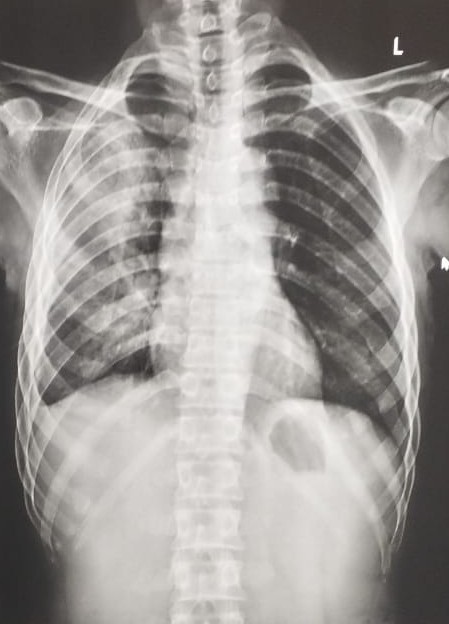

| 207 | IGGMC, Nagpur, Nagpur | P2 | 29-4265 | SHUBHAM MARATHE | Consent taken on Paper | 27 Yrs. |

Provisional Diag : LEFT SIDED CLINICALLY DIAGNOSED PLEURAL EFFUSION

Final Diag : LEFT SIDED CLINICALLY DIAGNOSED TUBERCULAR EMPYMA ON ATT FROM 9.11.2024 |

TB Case (Confirmed) | LEFT SIDED CP ANGLE BLUNTING | Abnormality visible on x-ray |

View |